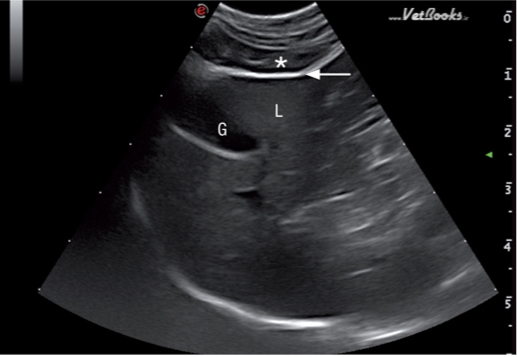

腹膜壁层在近场上呈现一条高回声亮线(图1)。器官表面的腹壁脏层又称为浆膜层,包裹在肠道外壁,胃的外壁,膀胱的外壁,脾脏和肝脏的外壁,也呈高回声的亮线(图2)。腹膜结缔组织连接腹腔各个器官,有3个双层腹膜结构,分布是网膜,肠系膜,韧带(图3)猫的镰状韧带位于肝的腹侧被脂肪组织所包裹,相较于肝脏实质的回声镰状韧带可呈无回声或低回声,偶尔呈高回声,它的质地更加粗糙些(图4)。肝脏包膜的高回声亮线是镰状韧带和肝脏实质的分界。而猫的分界线比较模糊,没有经验医生很难将镰状韧带和肝脏实质区分开。可能会将镰状韧带误认为是肝脏,在进行细针抽吸时吸出的不是肝脏组织而是脂肪。